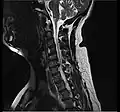

- Magnetic resonance imaging is the gold standard study for confirming a suspected LDH. With a diagnostic accuracy of 97%, it is the most sensitive study to visualize a herniated disc due to its significant ability in soft tissue visualization. MRI also has higher inter-observer reliability than other imaging modalities. It suggests disc herniation when it shows an increased T2-weighted signal at the posterior 10% of the disc. Degenerative disc diseases have shown a correlation with Modic type 1 changes. When evaluating for postoperative lumbar radiculopathies, the recommendation is that the MRI is performed with contrast unless otherwise contraindicated. MRI is more effective than CT in distinguishing inflammatory, malignant, or inflammatory etiologies of LDH. It is indicated relatively early in the course of evaluation (<8 weeks) when the patient presents with relative indications like significant pain, neurological motor deficits, and cauda equina syndrome. Diffusion tensor imaging is a type of MRI sequence used for detecting microstructural changes in the nerve root. It may be beneficial in understanding the changes that occur after herniated lumbar disc compresses a nerve root, and might help in differentiating the patients that need surgical intervention. In patients with a high suspicion of radiculopathy due to lumbar disc herniation, yet the MRI is equivocal or negative, nerve conduction studies are indicated.[44] T2-weighted images allow for clear visualization of protruded disc material in the spinal canal.

-

MRI scan of cervical disc herniation between C5 and C6 vertebrae -

MRI scan of cervical disc herniation between C6 and C7 vertebrae -